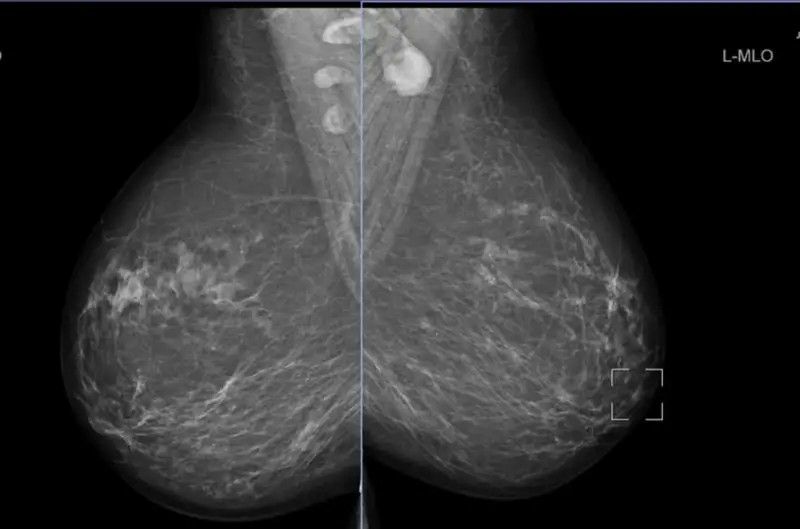

ضایعات بدخیم کبدی و مدیریت آنها: در میان ضایعات بدخیم کبد، کارسینوم هپاتوسلولار (HCC) شایعترین نوع سرطان اولیه کبد است که اغلب در بیماران مبتلا به سیروز یا عفونت مزمن ویروسی کبد دیده میشود. در تصویربرداری CT و